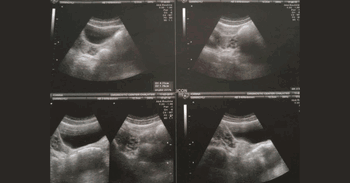

Woman Shares What Its Like to Live Without a Vagina

Image source: Joanna Giannouli